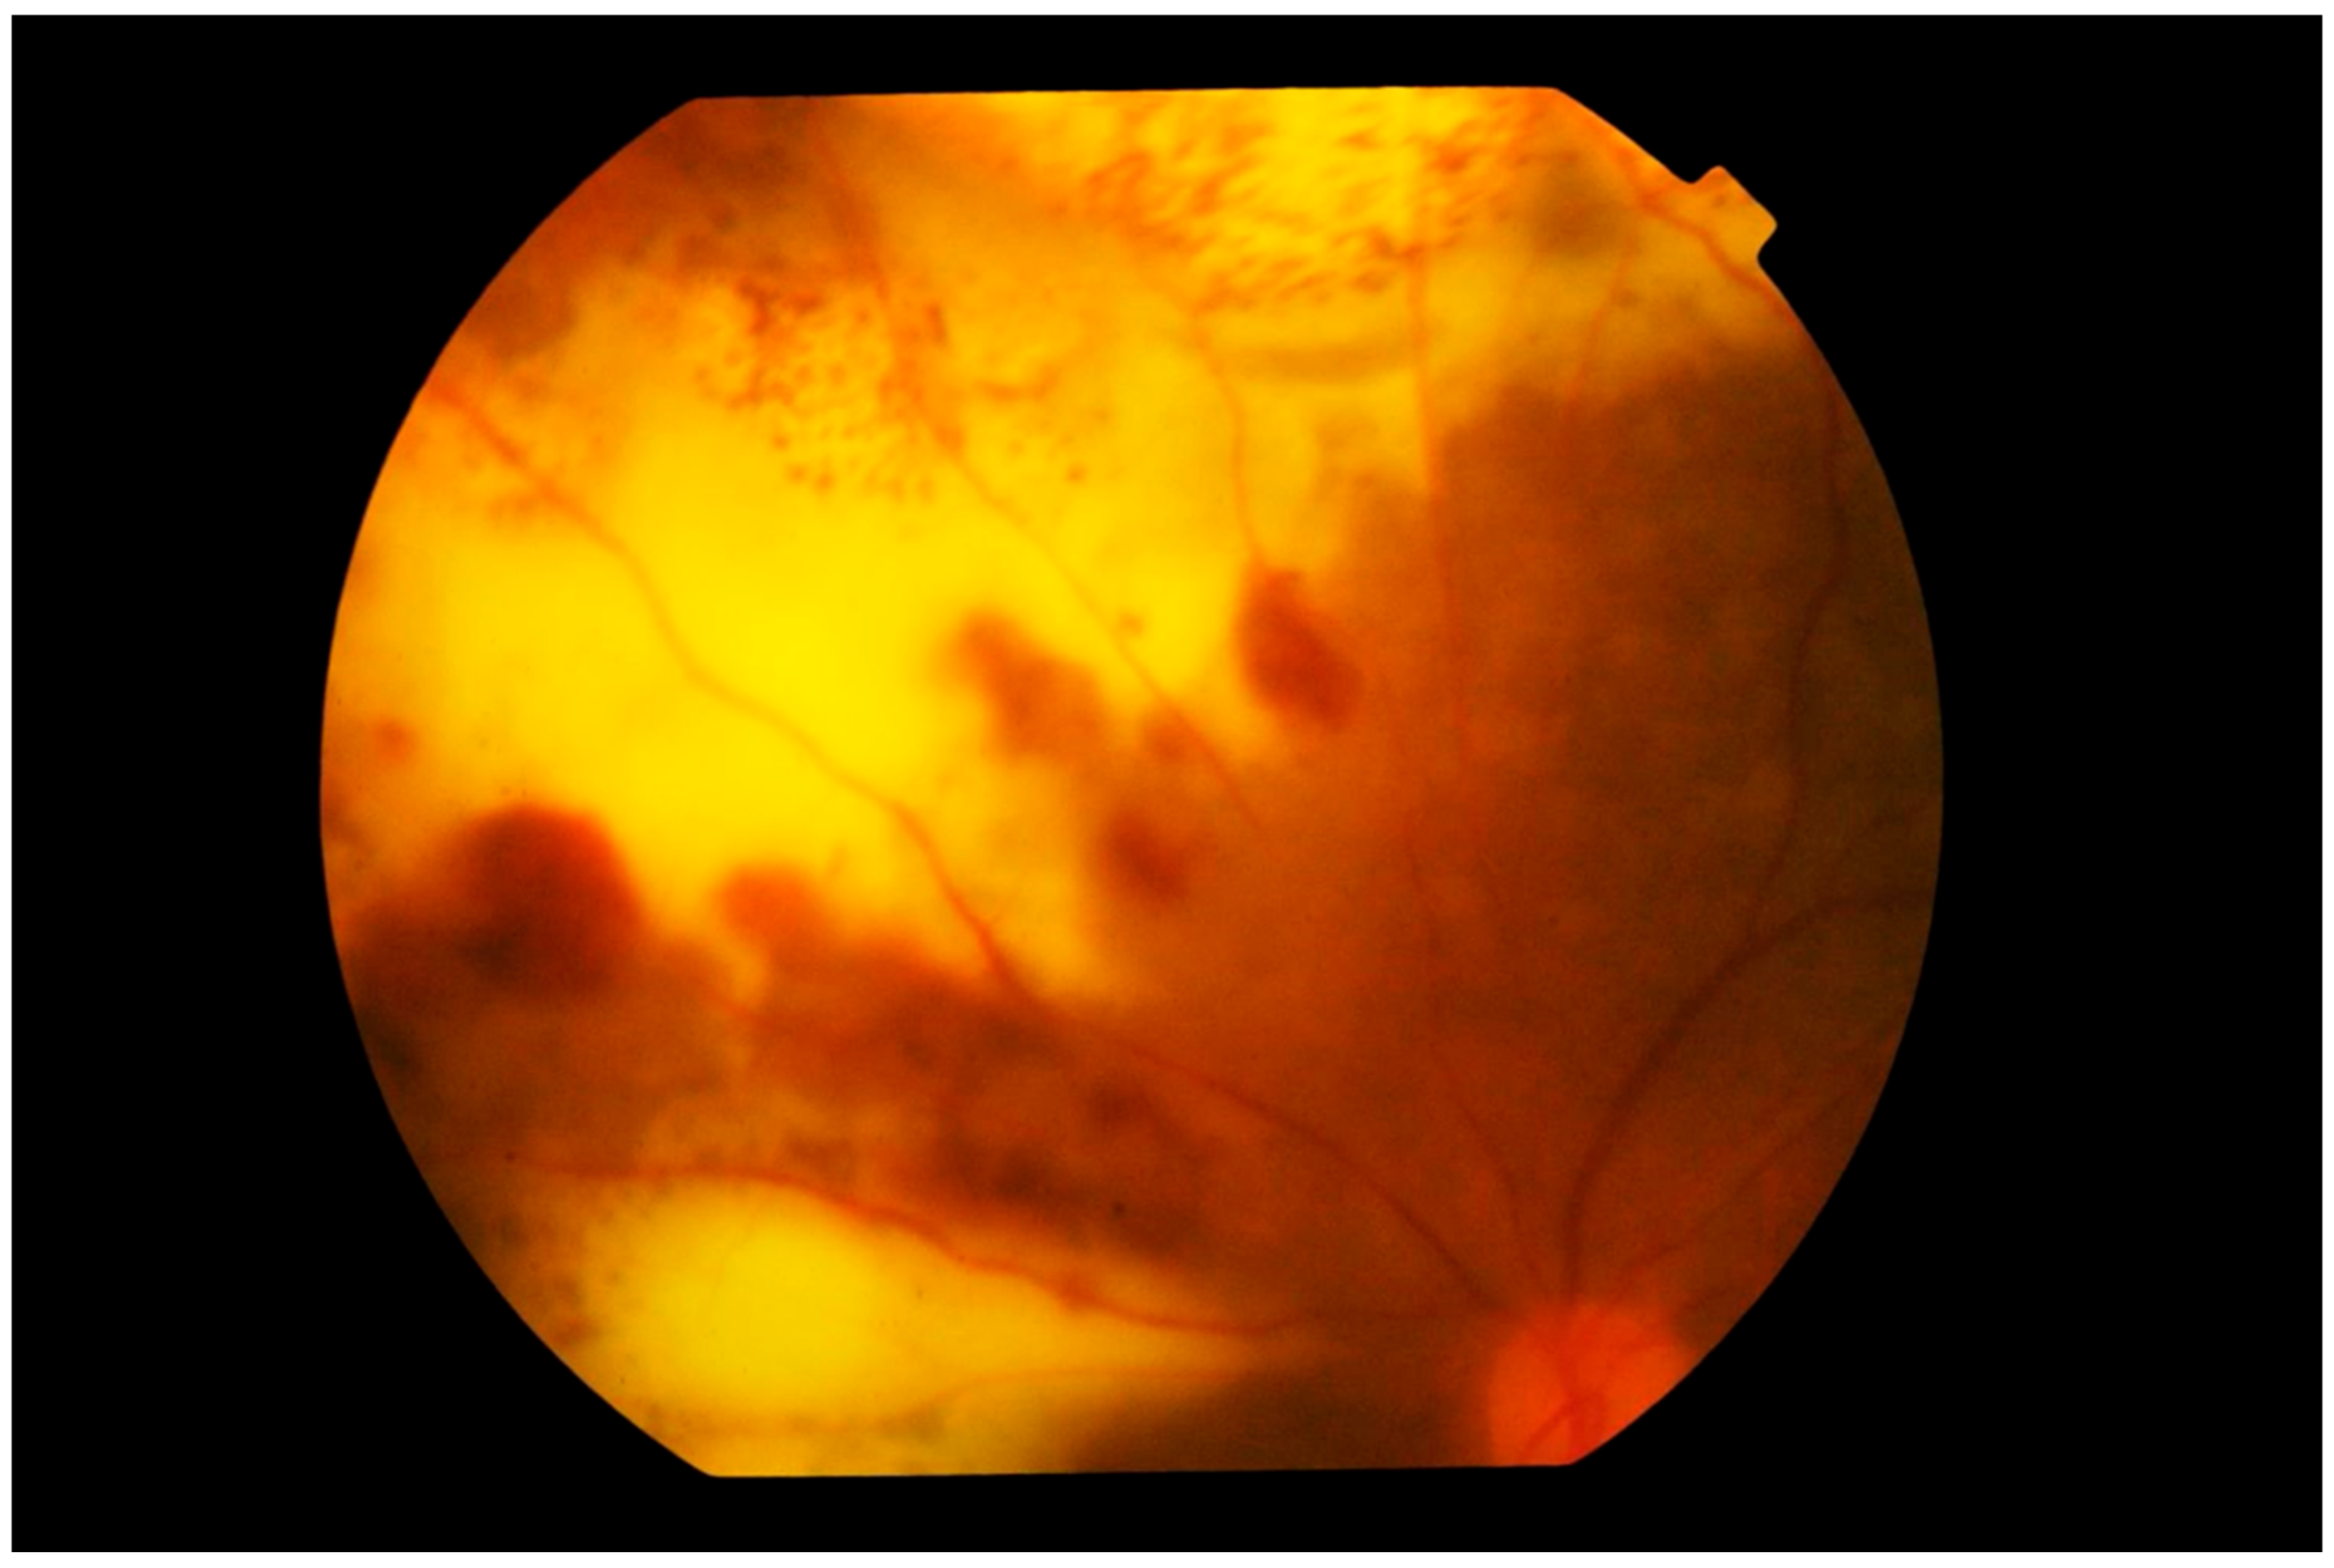

4.1. Imaging

4.1.3. Fluorescein Angiography

4.1.4. Indocyanine Green Angiography